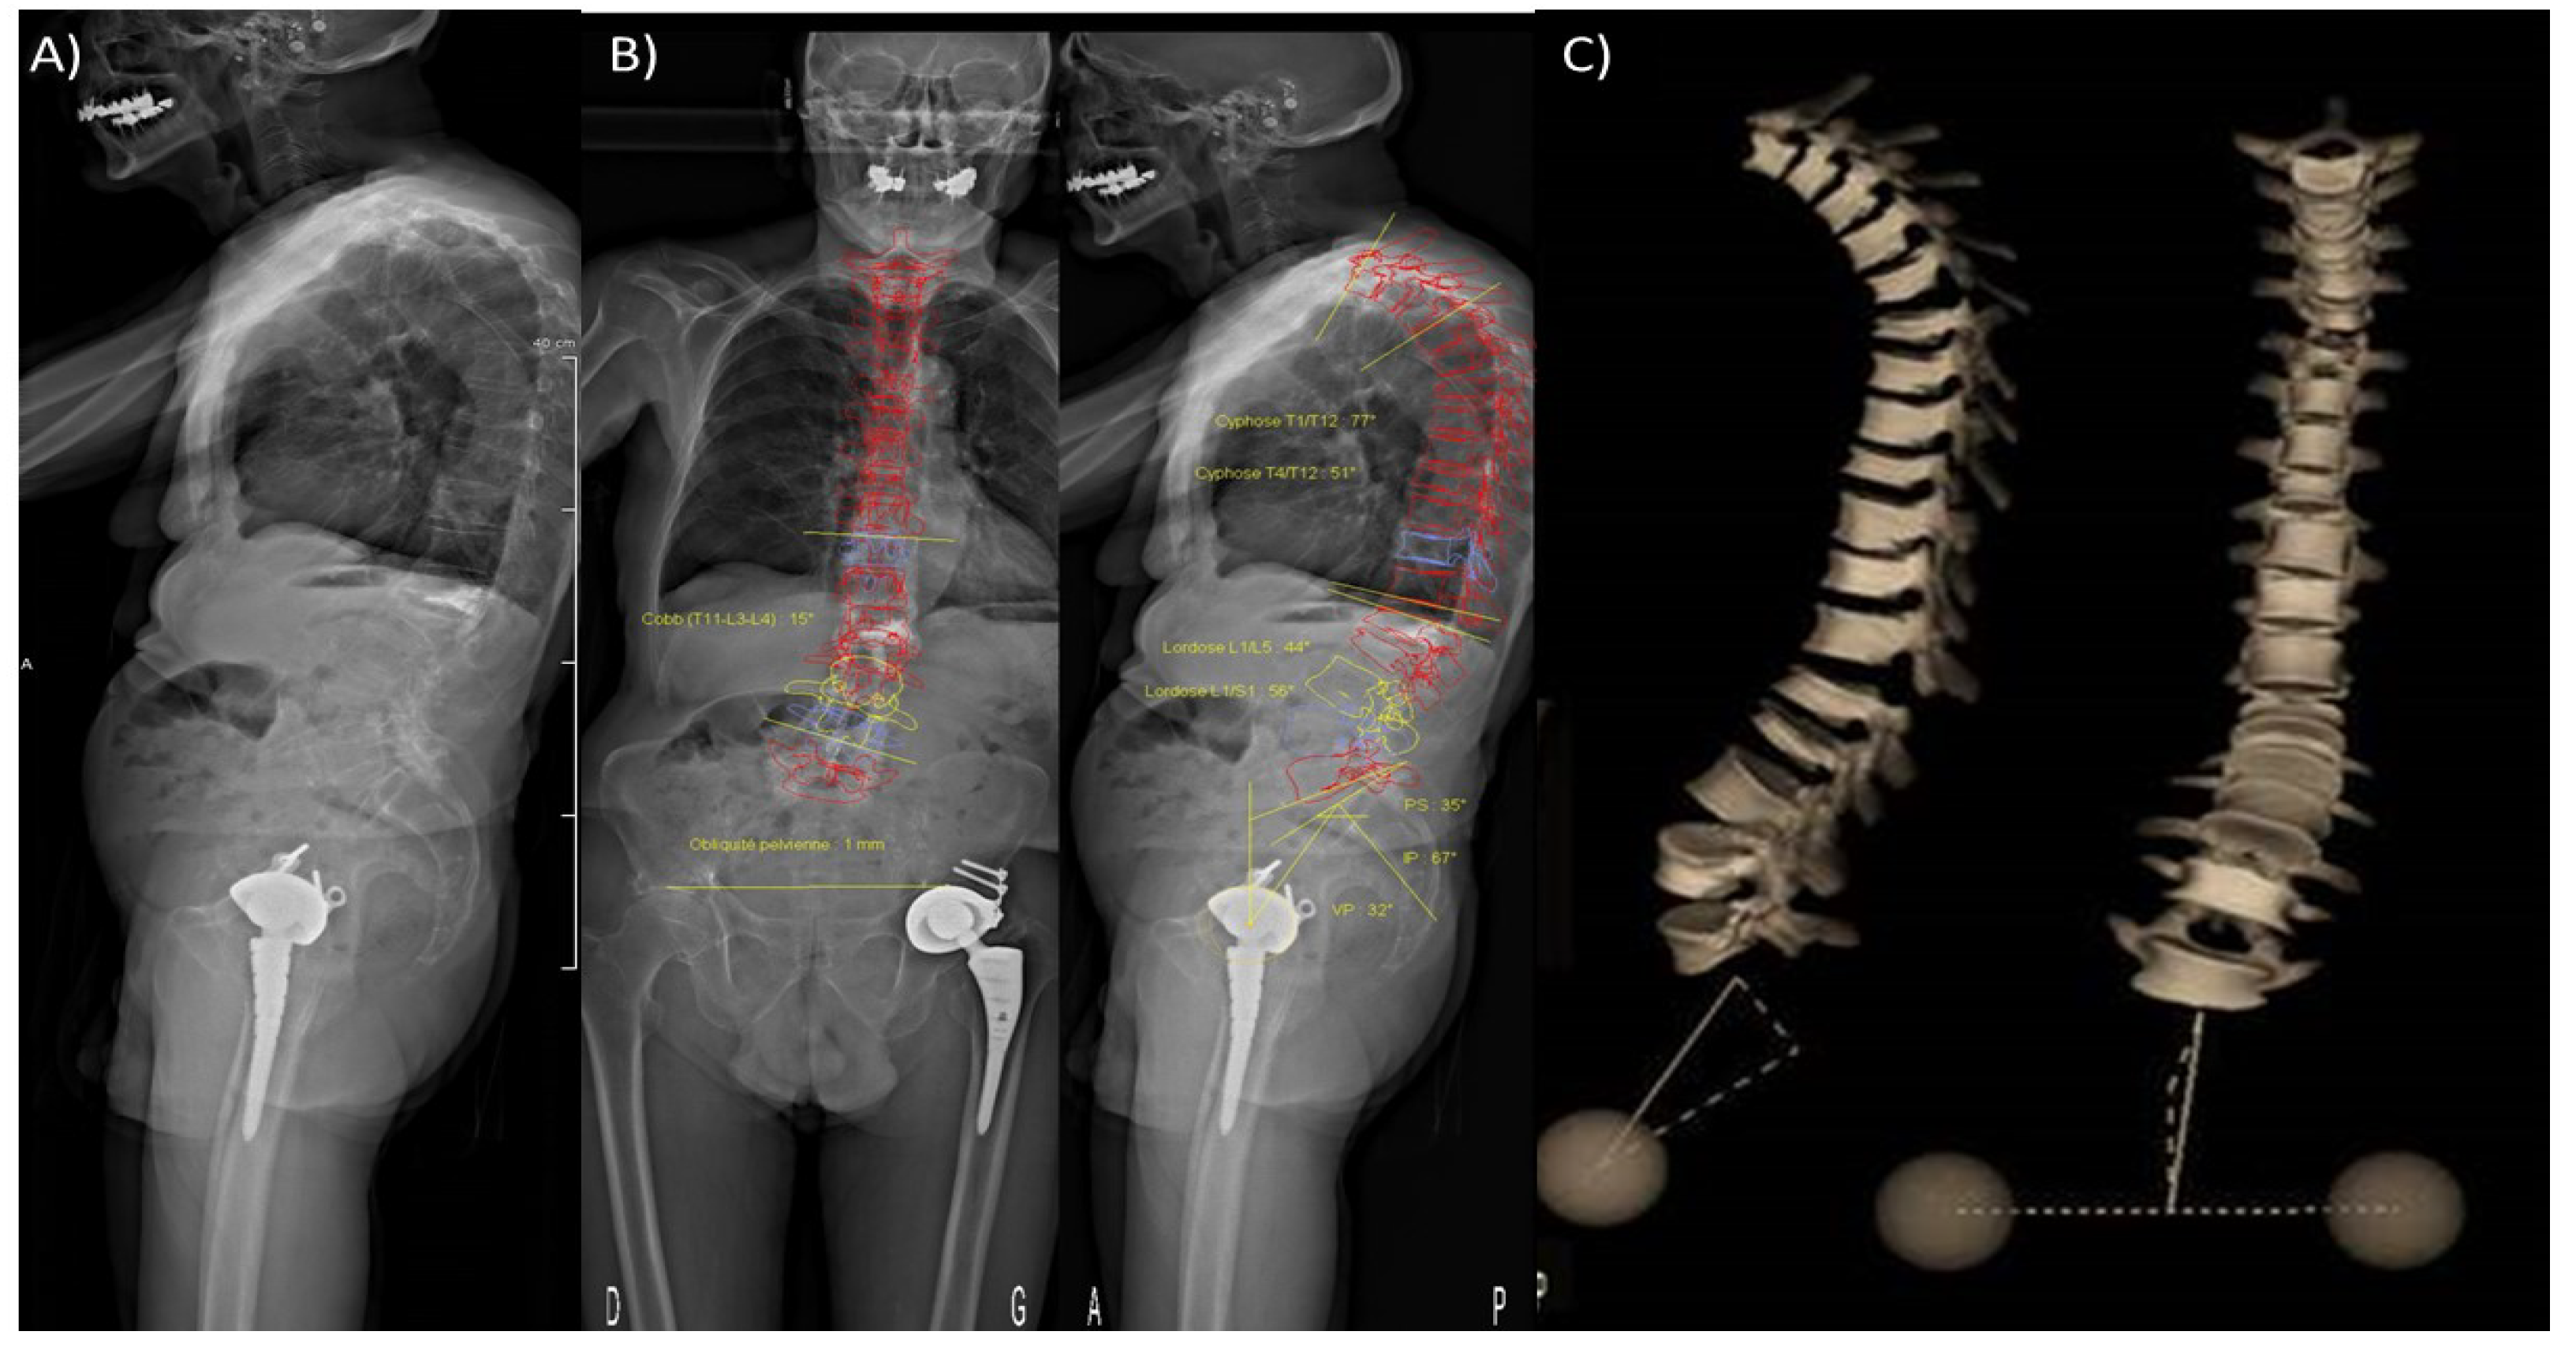

- Dubousset, J.; Charpak, G.; Dorion, I.; Skalli, W.; Lavaste, F.; DeGuise, J.; Kalifa, G.; Ferey, S. A new 2D and 3D imaging approach to musculoskeletal physiology and pathology with low-dose radiation and the standing position: The EOS system. Bull. Académie Natl. Méd. 2005, 189, 287–300. [Google Scholar] [CrossRef]

- Skalli, W.; Mitton, D.; Rouch, P.; Dubousset, J. Biomechanics and Spinal Modelling. In Spinal Anatomy: Modern Concepts; Vital, J.M., Cawley, D.T., Eds.; Springer International Publishing: Cham, Germany, 2019; pp. 491–503. [Google Scholar]

- Deschênes, S.; Charron, G.; Beaudoin, G.; Labelle, H.; Dubois, J.; Miron, M.-C.; Parent, S. Diagnostic Imaging of Spinal Deformities: Reducing Patients Radiation Dose with a New Slot-Scanning X-ray Imager. Spine 2010, 35, 989–994. [Google Scholar] [CrossRef]

- Brosses, E.S.-D.; Jolivet, E.; Travert, C.; Mitton, D.; Skalli, W. Prediction of the Vertebral Strength Using a Finite Element Model Derived from Low-Dose Biplanar Imaging: Benefits of Subject-Specific Material Properties. Spine 2012, 37, E156–E162. [Google Scholar] [CrossRef]